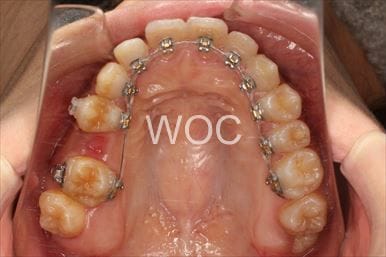

治療中3

-